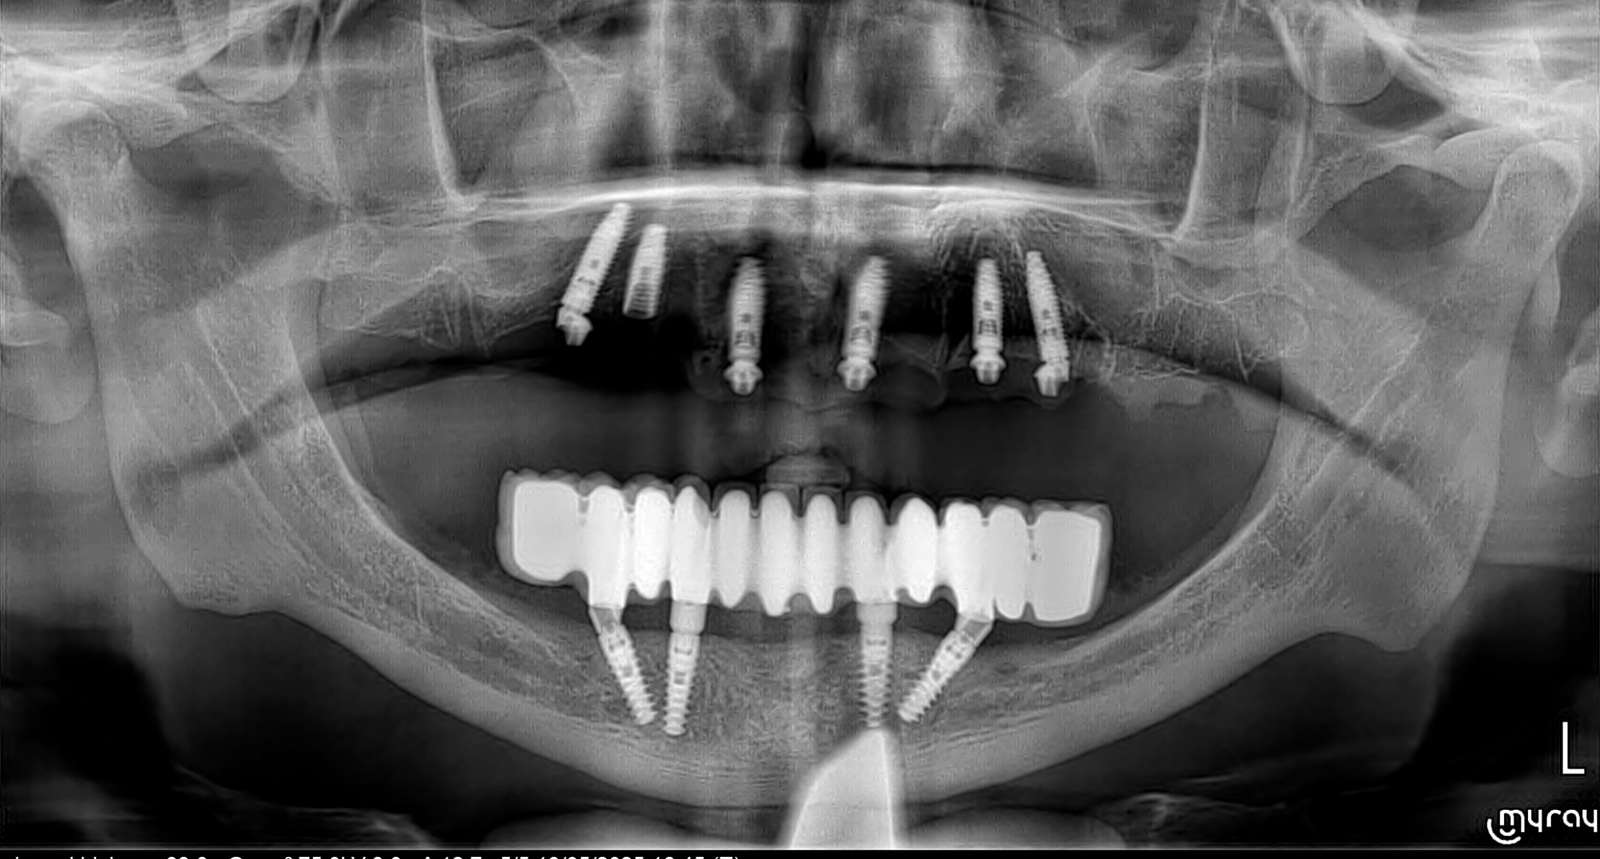

Réhabilitation complète avec mise en charge immédiate (4 implants bas / 6 implants haut)

Le patient se présente avec des dents qui bougent, en haut et en bas.

Nous avons commencé par la mâchoire inférieure avec 4 implants et une mise en charge immédiate.

Trois mois après, le haut a été fait avec le même principe avec 6 implants.

Cette fois-ci, il existait un déficit osseux, résolu par une technique d’expansion sans avoir recours à la greffe d’os.

Les prothèses réalisées sont vissées, ce qui permet de les enlever, les nettoyer une fois par an, ou résoudre n’importe quel problème.